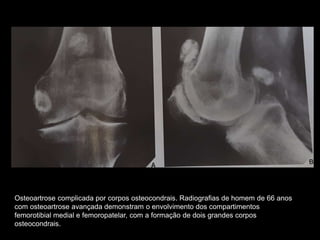

Osteoartrose complicada por corpos osteocondrais. Radiografias de homem de 66 anos

com osteoartrose avançada demonstram o envolvimento dos compartimentos

femorotibial medial e femoropatelar, com a formação de dois grandes corpos

osteocondrais.